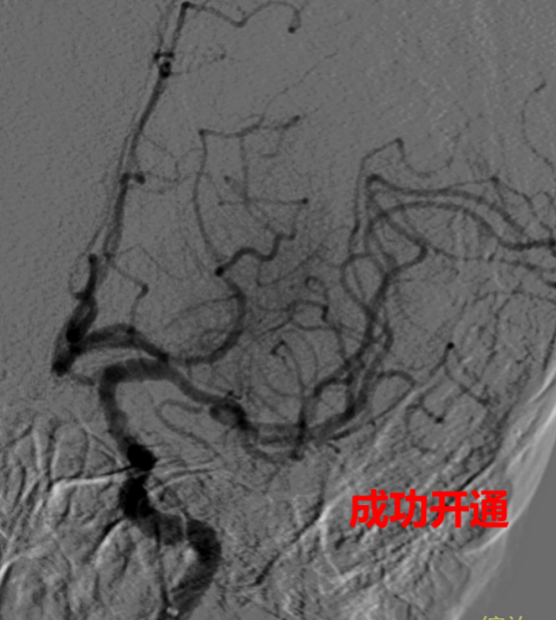

在取得家属的知情同意后,神经医学中心何旭英主任介入团队立即对唐叔予以静脉溶栓、导管室机械取栓等系列抢救治疗。幸运的是,因为发现及时、抢救到位,唐叔被堵塞的脑血管迅速得以开通,脑组织的血流得以恢复。

脑血管造影,显示介入手术开通后血流恢复

术后返回病房,唐叔恢复意识,右手右脚能抬起来了,也可以说话了。当天半夜唐叔的儿子从梅州赶过来,看到父亲转危为安,心里的石头落下了地,“真是很幸运,在医院里得到了及时抢救。真的很难想象在家的话,会发生什么后果。”